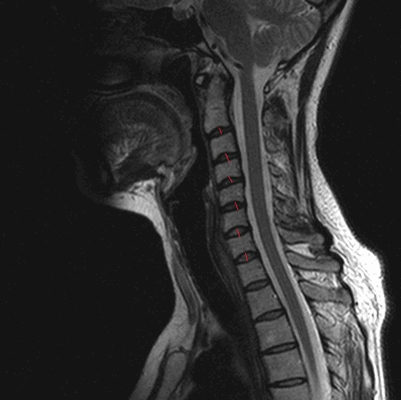

МРТ шейного отдела позвоночника. Стеноз позвоночного канала . Сагиттальная Т2-взвешенная МРТ.

МРТ позвоночника в шейном отделе, оценка высоты дисков (указана красными линиями)